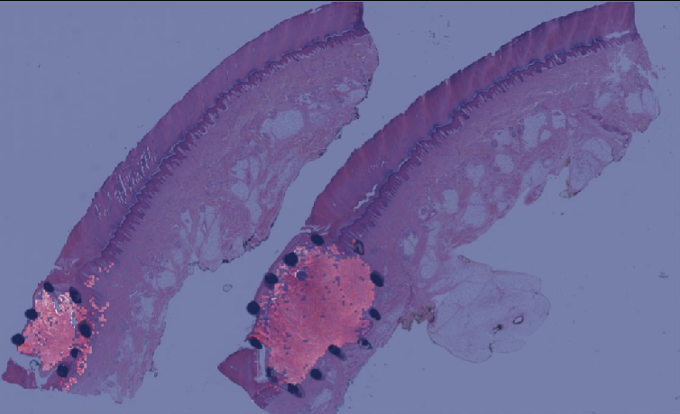

Explanations for the figures. Figure 2 shows one representative sample of annotations (black dot regions) as well as without annotations. Visualization maps of two samples from the melanocytic skin tumor dataset are shown in figure 3 and figure 4. Figure 3 shows the three types of figures of the largest ROI region from melanoma found by the proposed method. Figure 4 is the same for the nevus sample. The overlap map highlights top-ranked patches in a WSI and masks other area with a transparent blue color. The percentage of highlighted patches equals (the annotated ratio). The boundary map shows the boundary of the largest ROI cluster based on the highlighted patches, where the highlighted patches are clustered by OPTICS algorithm from Ankerst et al. (1999). The last one is a heatmap where red covers regions that have high predicted scores and blue covers regions that have low predicted scores.

(a) Boundary of the largest predicted ROI region

(b) Overlay

(c) Heatmap